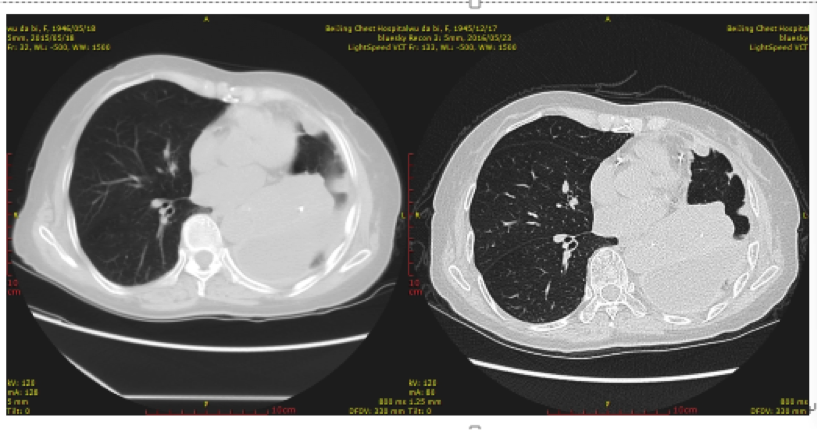

患者的胸部CT影像图治疗效果对比见下,左图为入组临床研究前,右图为治疗后。

无标题.png